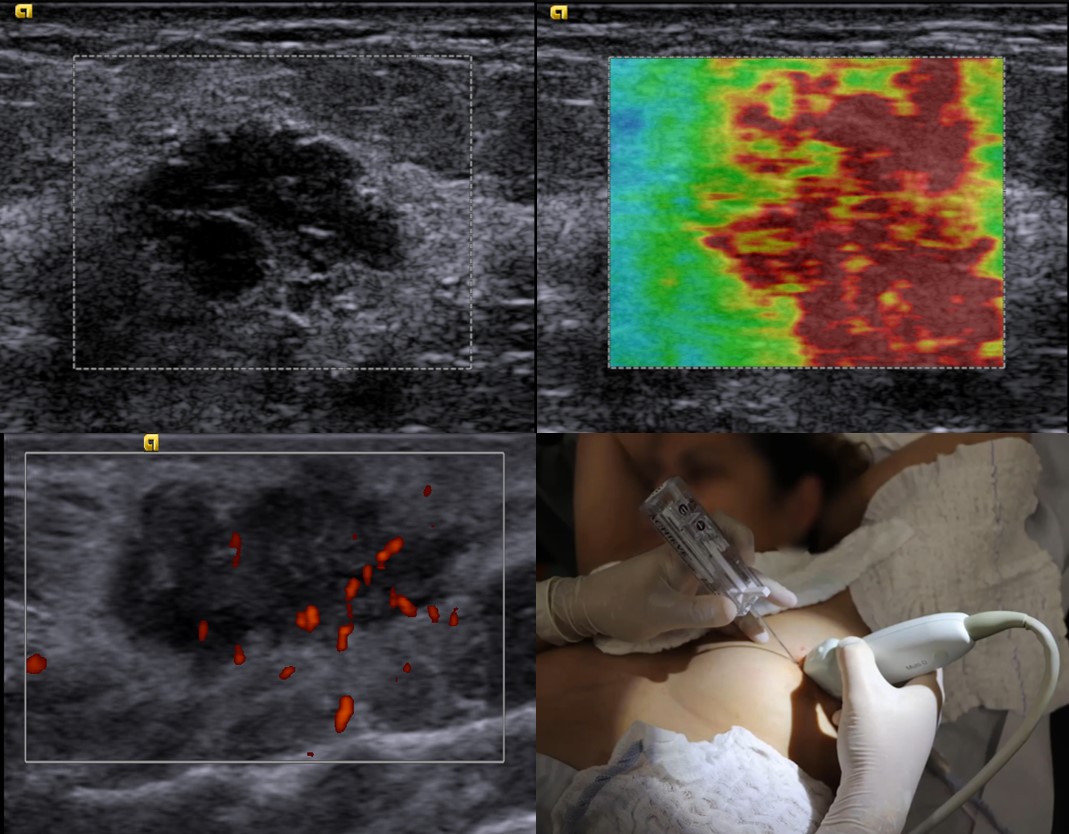

Ultrassonografia mamária - 10 vagas

Local: Seção de ultrassonografia do Hospital da Mulher "Prof. Dr. José Aristodemo Pinotti" - CAISM - Unicamp